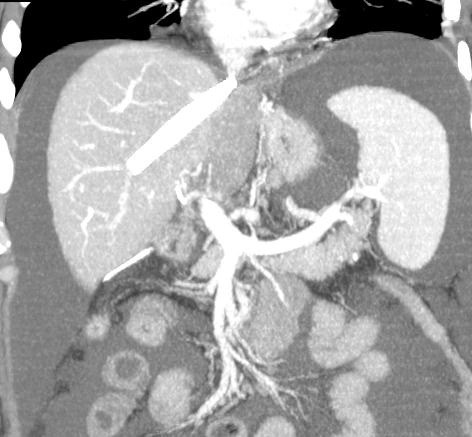

肝右静脉血栓,肝中静脉狭窄 |